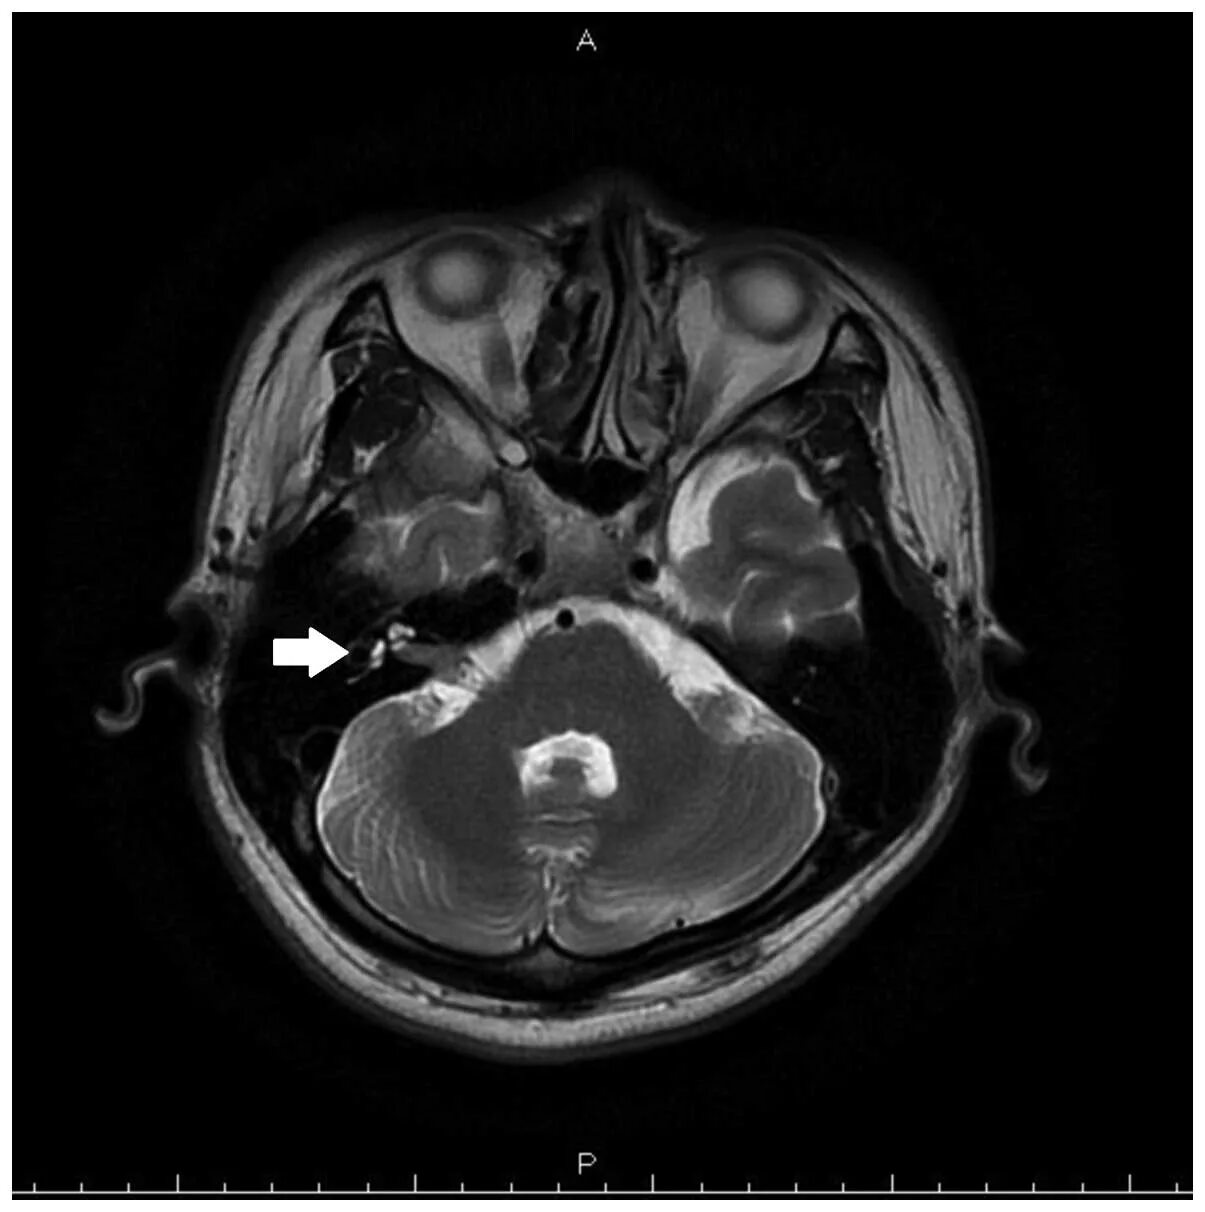

Нейроваскулярный конфликт нерва